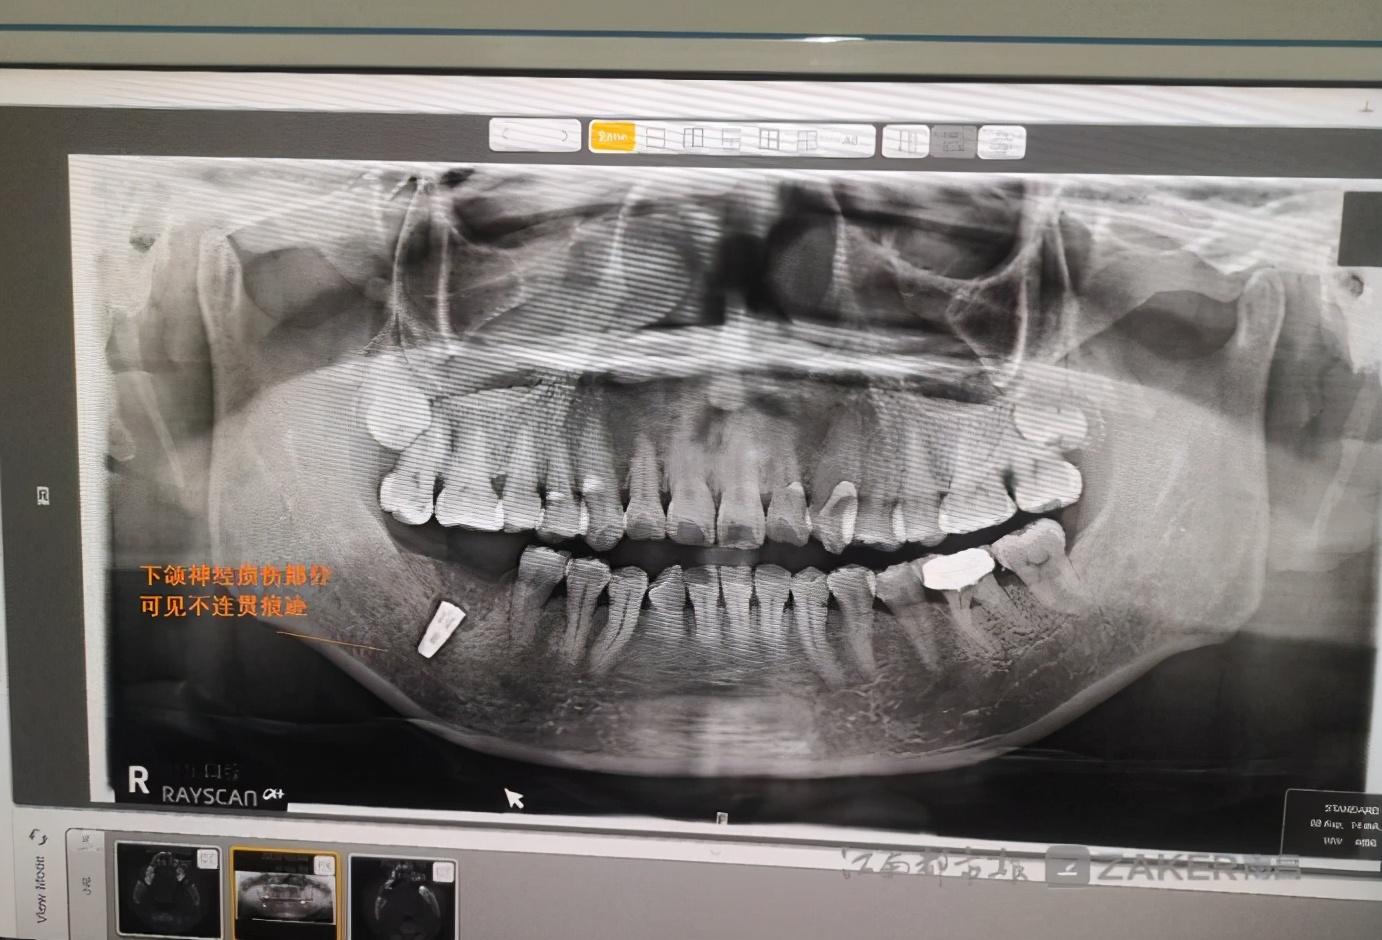

消炎針打完后,下頜的麻木感仍然存在。在家人的陪同下,繆女士前往專業(yè)口腔醫(yī)院檢查。在一份由南昌大學(xué)附屬口腔醫(yī)院 9 月 29 日出具的診斷證示,"46 牙可見種植體植入影像,下頜神經(jīng)管上壁可見不連續(xù)影像。" 繆女士告訴記者,經(jīng)檢查診斷后得知,自己的下頜神經(jīng)因種植牙手術(shù)受到損傷,這是下頜麻木的根本原因。